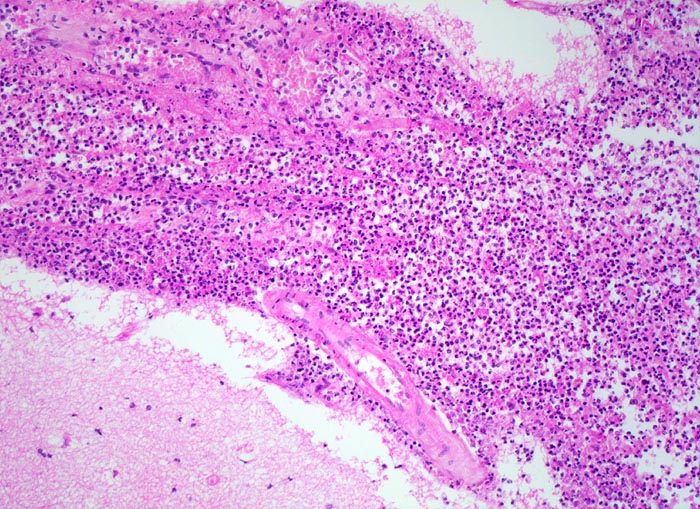

PathoPic ID 5189 - Eitrige Leptomeningitis

Eitrige Leptomeningitis

Entzündung infektiös

Meningen

Nervensystem

Der Subarachnoidalraum ist erweitert und angefüllt mit massenhaft neutrophilen Granulozyten (=Eiter).

Hirnrinde.

Bronchopneumonie. Nachweis von Pneumokokken im Abstrich von der Hirnoberfläche und von der Lunge.

Kopfschmerzen seit 3 Tagen mit zunehmender Bewusstseinseintrübung, Fieber. Diabetes mellitus. Patientin stirbt kurz nach Spitaleintritt.

100